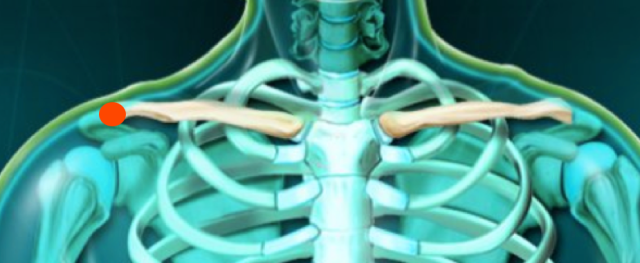

Rot interne passive ACIl faut alors confirmer l’hypothèse par le test de déplacement horizontal passif vers l’autre épaule

Add horizontale ACTraitement :

Massage transversal profond pour les ligaments superficiels :

Infiltrations pour les ligaments profonds ou en cas d’échec du MTP (voir ci-dessus)

Infiltration ACIl faut parfois infiltrer sous contrôle radiologique, surtout si l’articulation est arthrosée.